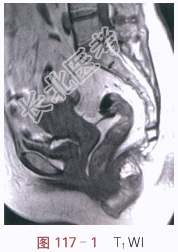

(1)症状:女,59岁,不规则阴道流血2月余。

(2)体格检查:诊断性刮宫未见异常。

影像学资料如图117-1~图117-5所示。

读片分析:子宫稍增大,内膜弥漫性增厚,结合带中断。增强扫描后,增厚的内膜呈不规则强化,局部浸润超过肌层1/2厚度。